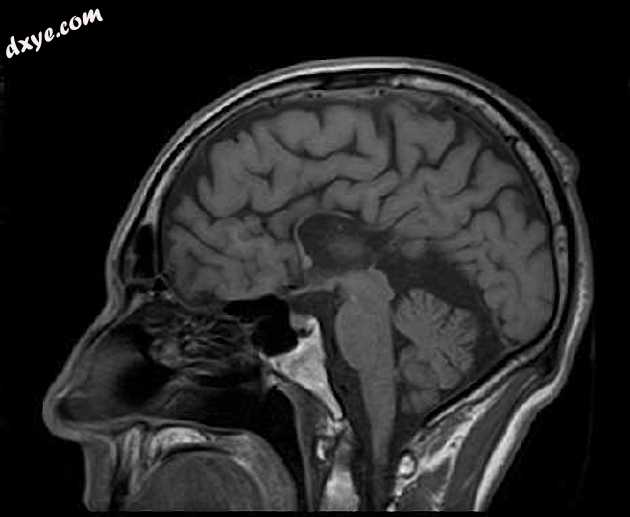

Sagittal T1

MRI序列显示:

胼胝体弥漫性变薄

侧脑室的平行体

主要在右侧(头畸形)的三角和枕角扩张,在轴向序列上形成“泪珠”构型

小额角

半球间裂增宽

扩张的高位第三脑室

矢状 T1 上脑回的太阳射线外观

扩张的小脑上池

注意右眼假体。